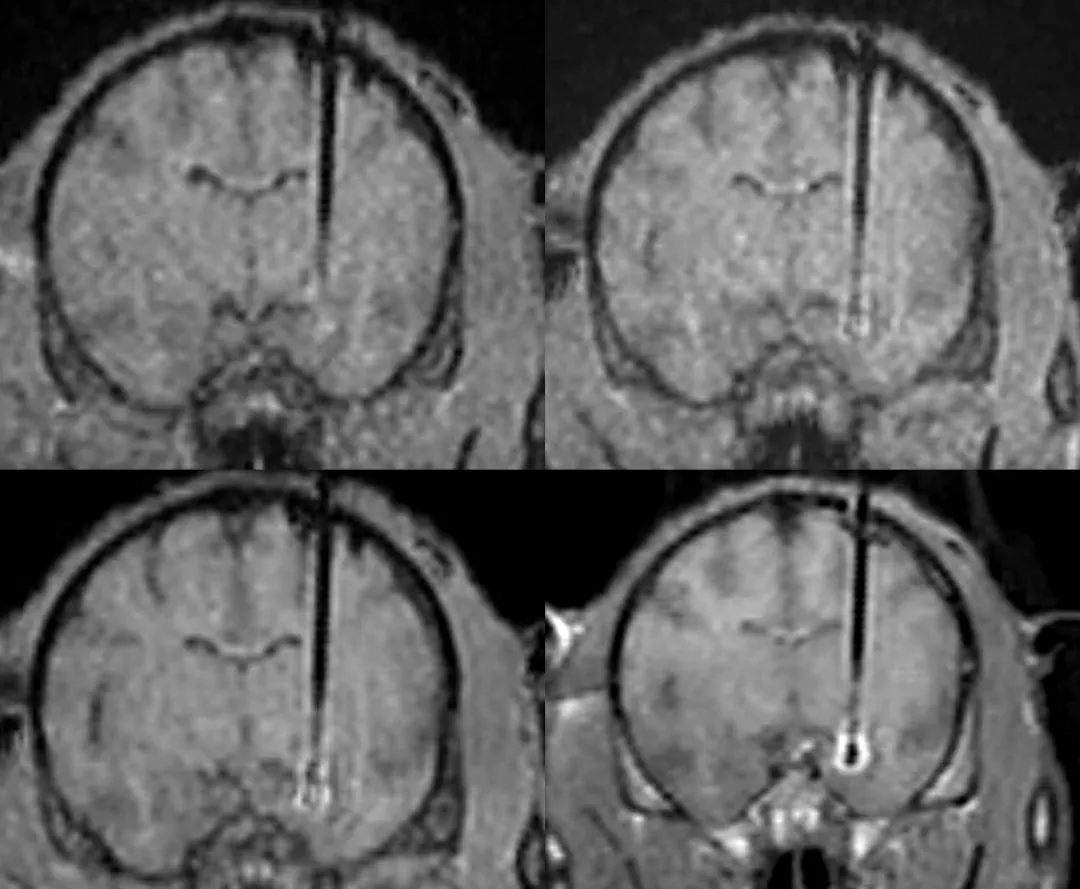

实时术中MRI导航技术:助力FDA批准首个AADC缺乏症基因疗法